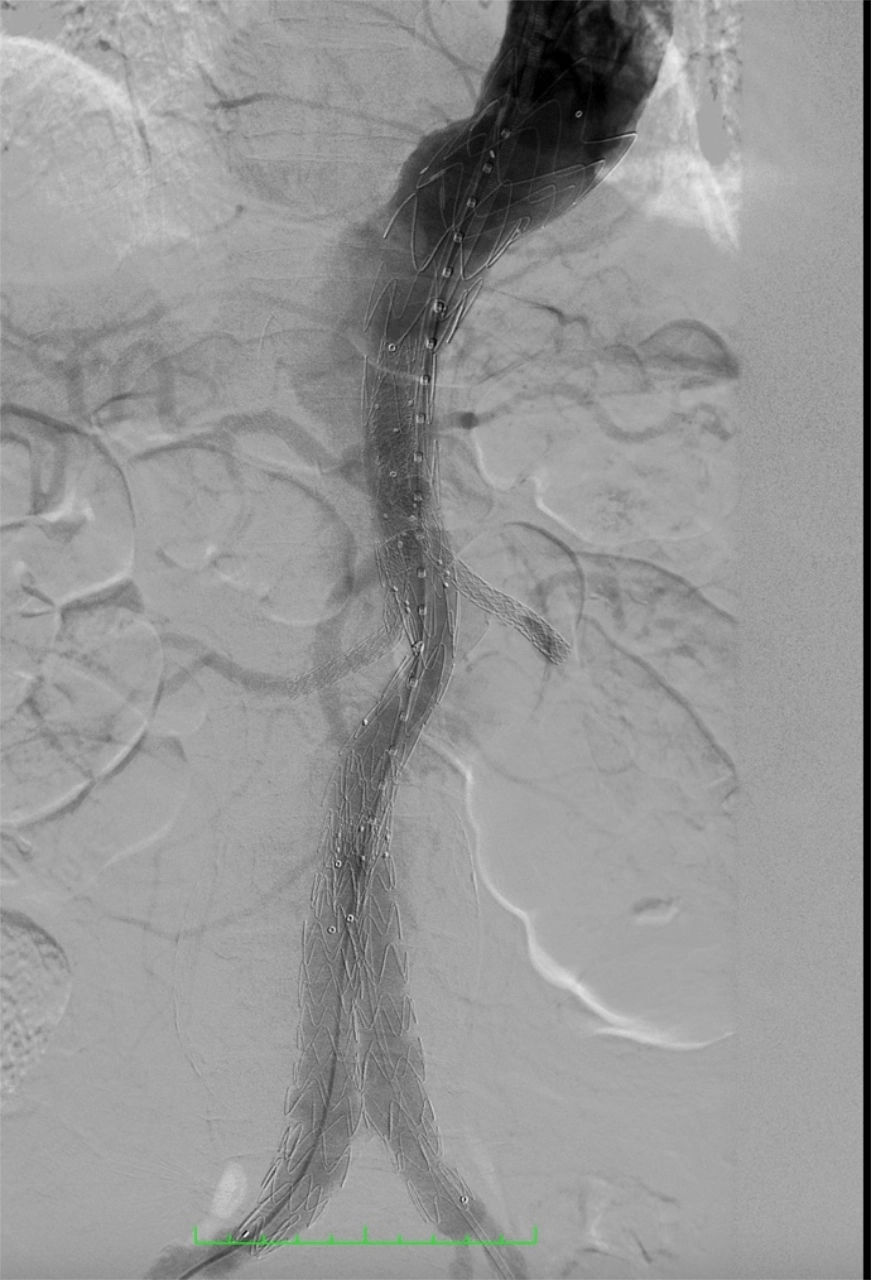

The procedure involved deployment of a custom-made E-xtra Design Multi-branch (EDM) stent graft, with meticulous cannulation and sequential stenting of the visceral arteries via the left brachial approach, including the right renal, left renal, superior mesenteric, and celiac arteries. The iliac limbs were subsequently deployed and optimized with post-dilation.

This complex intervention was performed as part of a staged repair strategy, with the second stage — Thoracic Endovascular Aortic Repair (TEVAR) completed on September 18, 2025 using the Medtronic Valiant system. The staged approach was carefully planned to reduce the risk of spinal cord ischemia during treatment of the extensive thoracoabdominal aneurysm.

Notably, the successful completion of this complex repair required the integration of endovascular technologies from two different device platforms, combining the Artivion E-xtra Design Multi-branch (EDM) stent graft for visceral branch preservation and the Medtronic Valiant thoracic stent graft system for the staged thoracic repair—demonstrating the importance of cross-platform innovation and collaboration to achieve optimal patient outcomes.